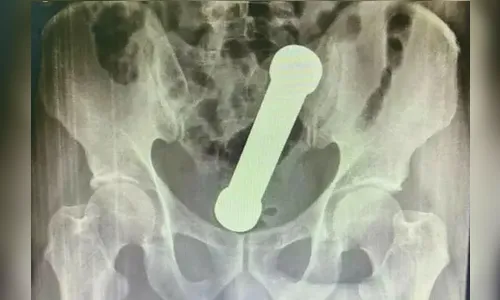

Ao realizarem um exame de raio-X, os médicos localizaram um peso de dois quilos, de cerca de 20 centímetros de comprimento, como os que são usados em academias de ginástica para exercícios de braço, dentro do homem.

O objeto estava entre o reto e o intestino grosso do paciente, que, depois do exame, admitiu ter introduzido o peso de academia para obter satisfação sexual.